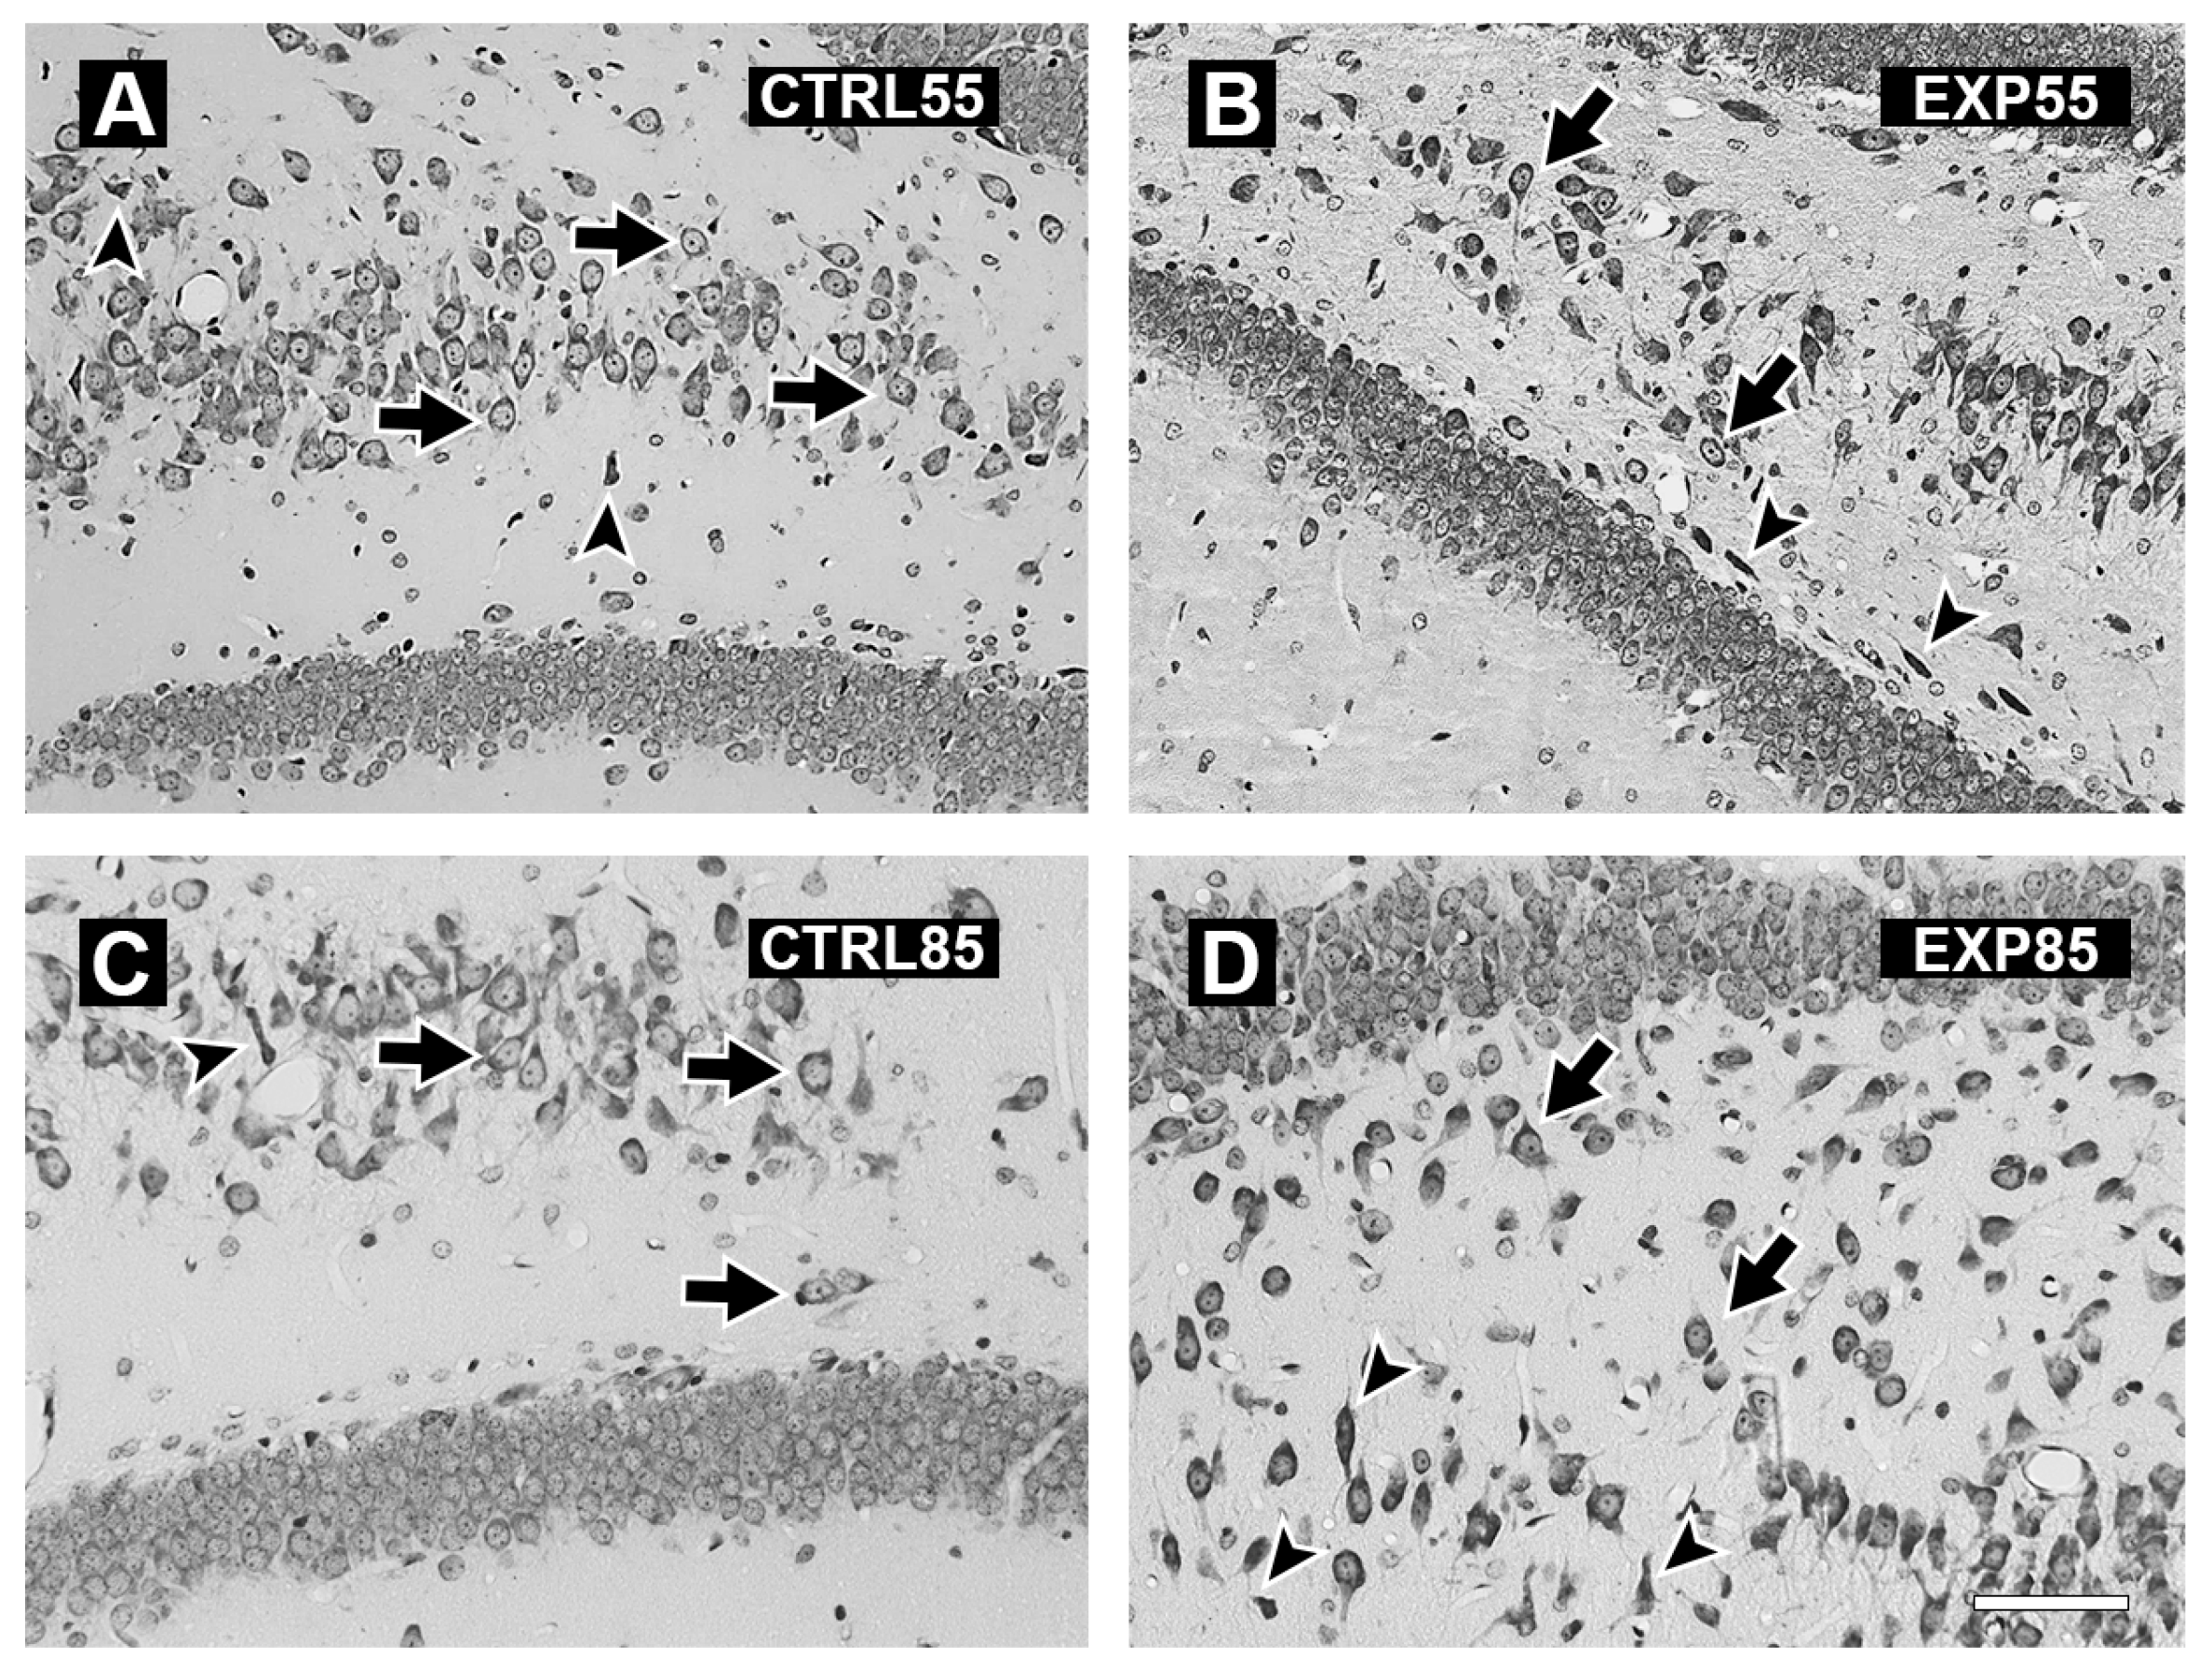

2.3. Histology

3. Results